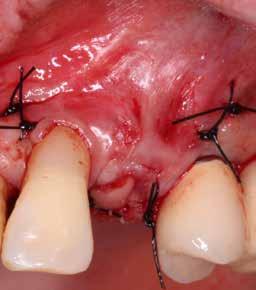

A 2020 januárjában elkezdett kezeléssorozat befejezését az év márciusában, hazánkba is begyűrűző Covid-19 pandémia késleltette, így kb. 6 hónap gyógyulás után láttunk hozzá az emergencia profil és a gingivális zenit ideiglenes koronával történő formázásához (11. és 12. kép). A 3 hetente végzett apró alakításokkal sikerült megfelelő ínyprofilt kialakítani, a „rózsaszín esztétika” a páciens számára is megfelelő volt. A bal felső nagymetsző fog meziális kompozit tömés cseréjét követően, individualizált nyitott kanalas lenyomati fejet készítettünk: az akrilát ideiglenes korona profilját átlátszó szilikonnal lemásoltuk, majd a körszimmetrikus gyári lenyomati fej és az ideiglenes korona kontúrja közötti hézagot folyékony kompozittal töltöttük ki (13. kép). Az így készített egyéni lenyomati fejjel vettünk lenyomatot a végleges, kerámialeplezésű cirkónium-dioxid vázas, átmenő csavaros rögzítésű koronához. (A fogtechnikai munkát Nébl Péter fogtechnikusmester készítette.), (14., 15., 16 és 17. képek).

A kész korona átadásakor a páciens elégedett volt az esztétikával, az azóta eltelt évben rendszeres kontrollokon jelent meg, melyek során meggyőződtünk a kemény- és lágyszövetek stabilitásáról (18. és 19. képek).